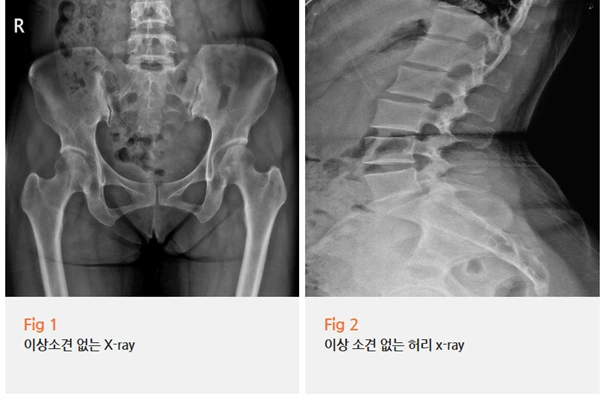

우선 당일 X-Ray를 비롯한 각종 검사를 시행했고,

이상근이 문제임을 확인했어요.